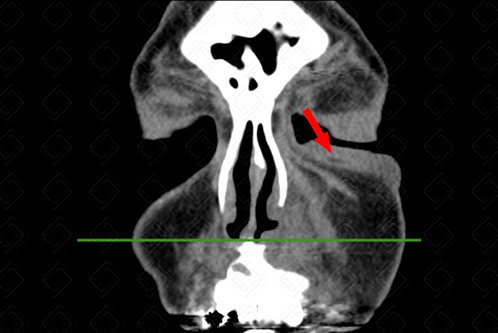

Descrição das figuras: Paciente com densificação dos planos adiposos na região maxilar esquerda, sem extensão orbitária, compatível com celulite de face (setas vermelhas).

• Tomografia computadorizada da face: Observa-se a densificação dos planos adiposos, podendo haver ainda a presença de coleções no estudo pós-contraste (figuras 1 e 2);